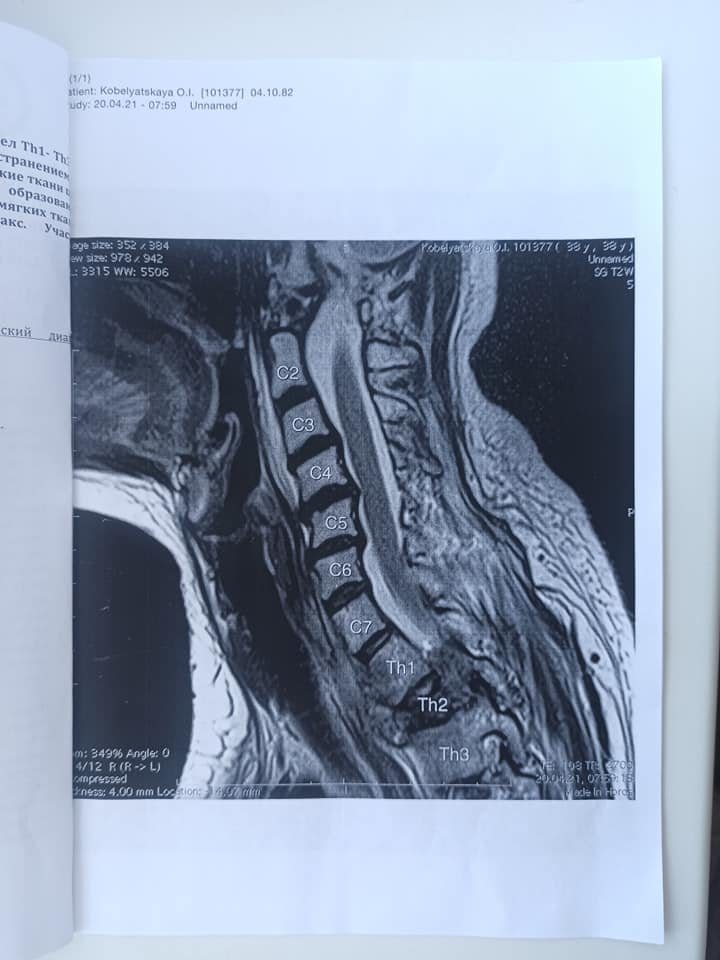

Жінка пройшла 1 курс хіміотерапії, але хвороба почала швидко прогресувати і призвела до патологічного компресійного перелому 2-го грудного хребця, також є осередки ураження в грудних хребцях. Тому на даний момент збережена часткова рухливість рук, а тіло нижче – паралізоване.